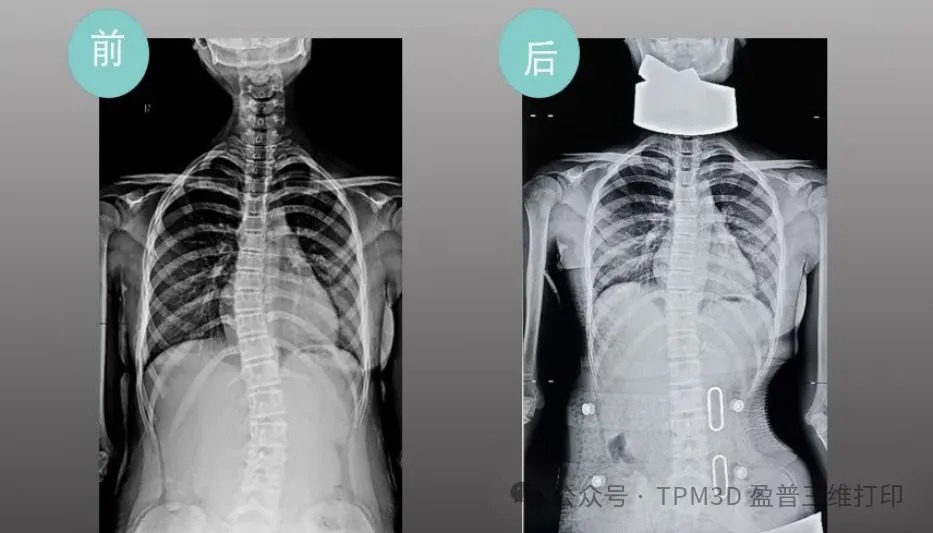

中心曾接診過這樣一位患者–五年級的小羅。當時,她因 25°脊柱側彎面臨治療困境,家庭經濟壓力更讓她的矯正之路舉步維艱。得知情況后,盈普技術團隊與中心迅速聯動,為小羅定制了專屬的 3D 打印矯形支具。從數據采集、支具設計到打印成型,全程僅用很短時間便完成。

令人欣喜的是,小羅佩戴支具僅一周,脊柱側彎度數就從 25°降至 10°以內。如今的她,身姿挺拔,重拾自信,家屬特意送來錦旗,上面 “仁心仁術治側彎”的話語,是對這份科技與醫療結合的溫暖最生動的注解。